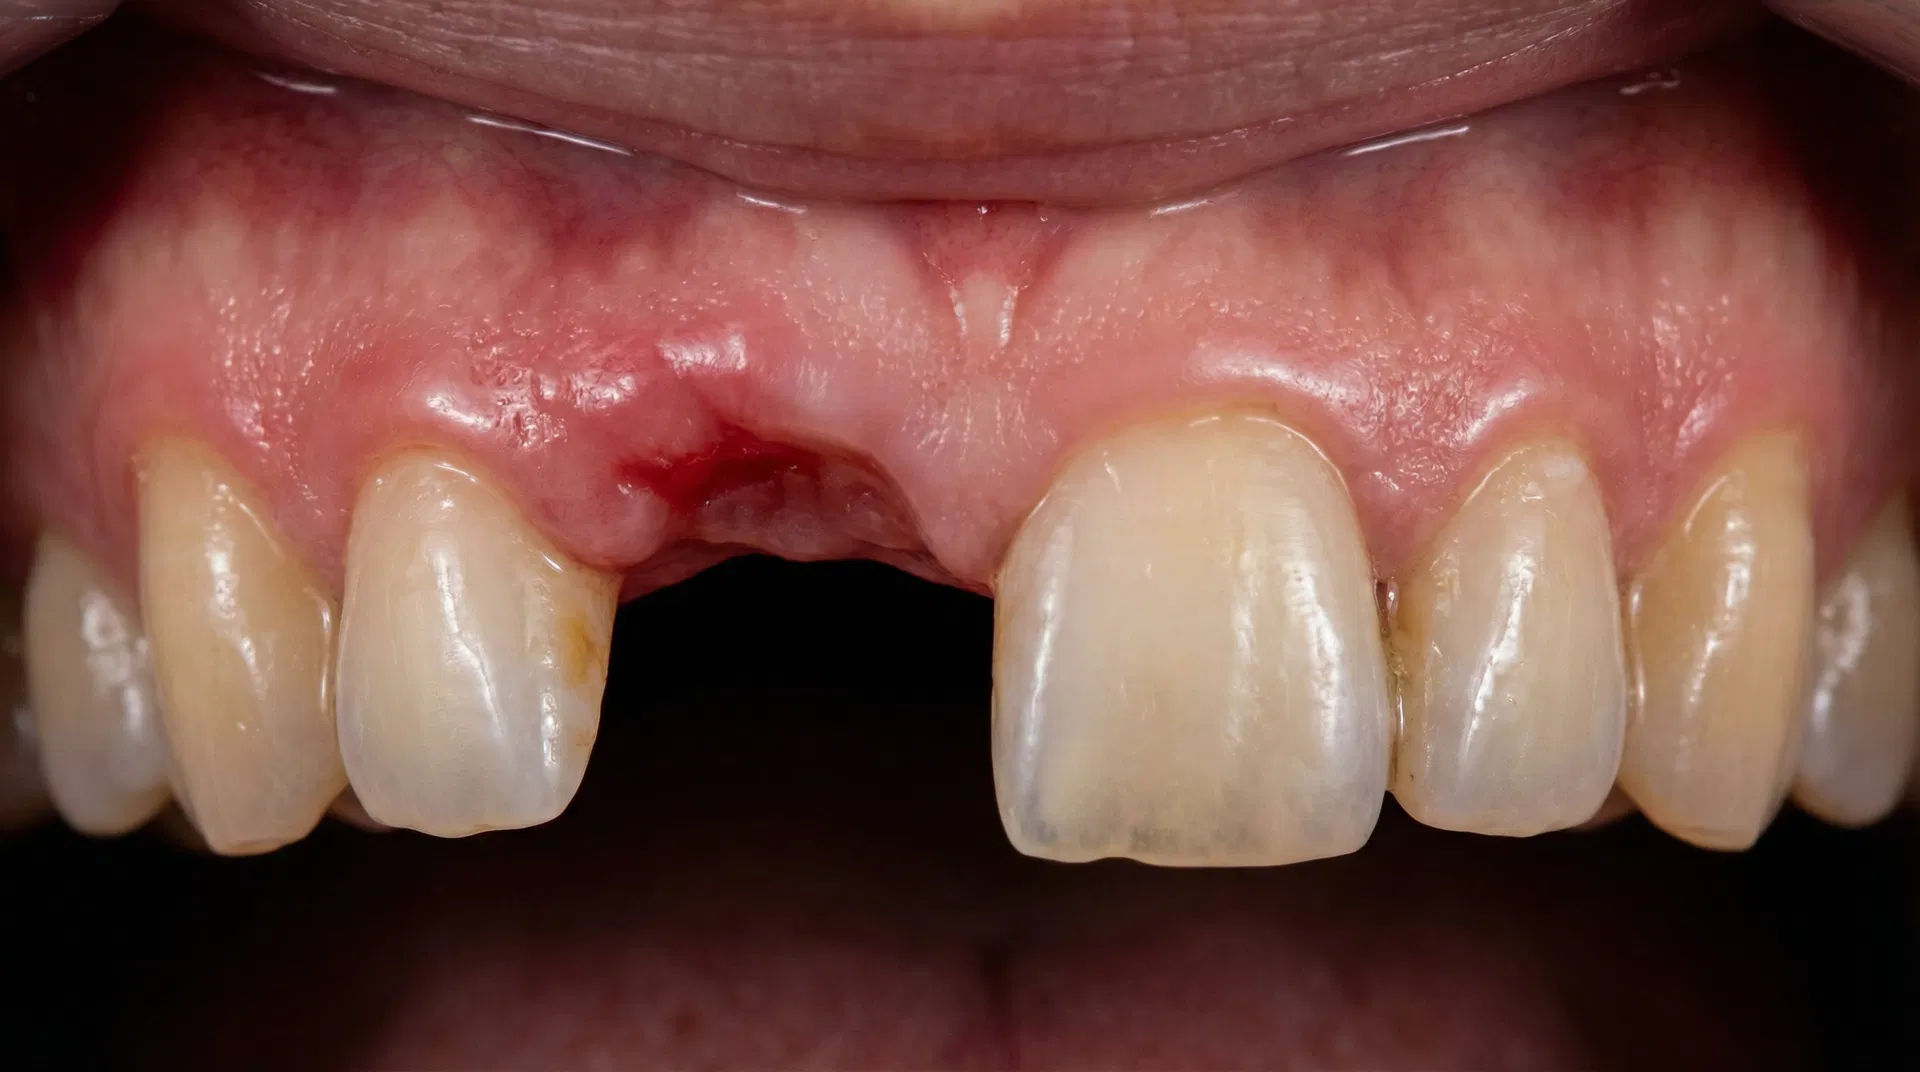

Before & After Transformations

See the life-changing results achieved by Dr. Nurein. Drag the slider to compare before and after treatment photos.

Note: Cases 2, 3, and 4 feature real patient results. Other cases are illustrative. Actual results may vary. Consult Dr. Nurein for a personalized assessment.

Single Tooth Implant

Missing upper front tooth replaced with a premium titanium implant and porcelain crown, restoring a natural, seamless smile.